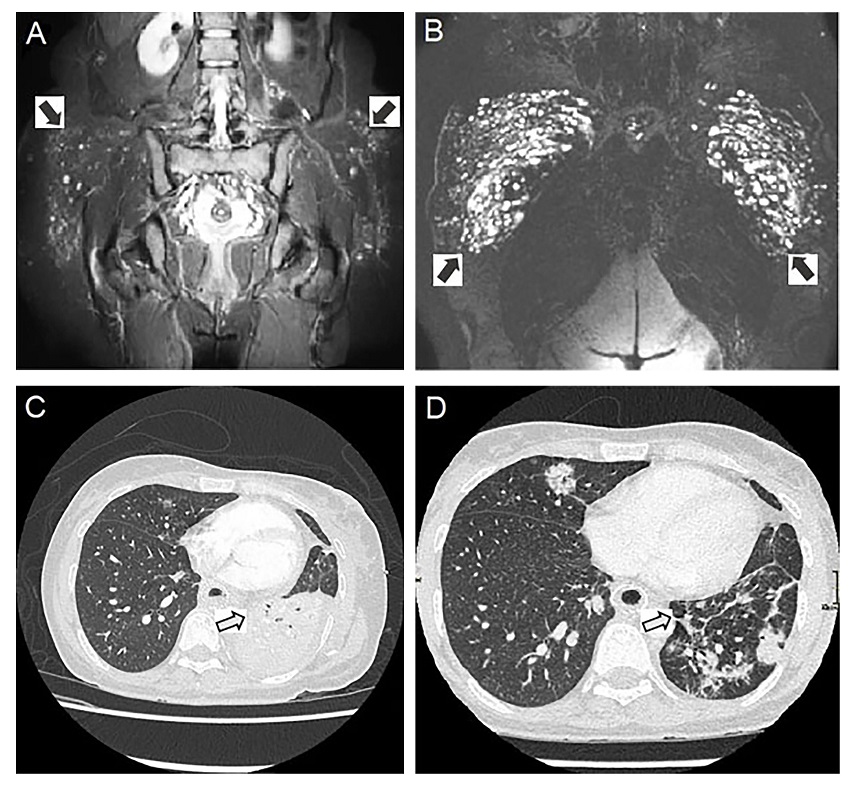

A 42-year-old female patient with a history of moderate smoking consumption, without comorbidities or significant family history, abdominal liposuction, buttock augmentation with biopolymer implants when she was 30 years old and augmentation mammoplasty with silicone implants on two occasions, the last one when she was 36-year-old. The current illness began at she was 37-year-old when she presented moderate dyspnea, dry eye, dry mouth, cough, arthralgia in the hands and relapsing fever. At that time, the previous clinical record described was 165 cm tall and weighed 64 Kg with vital signs of; Body temperature of 38.8 °C, pulse rate of 102 beats per minute, the respiration rate of 22 breaths per minute, and blood pressure of 110 / 78 mmHg, in the physical examination the clinical record described tenderness in metacarpophalangeal and proximal interphalangeal joints without swollen, and normal vesicular murmur in the upper third of both hemithorax, also fine crackles in two lower thirds in both hemithorax. Chest computed tomography (CT) showed reticulonodular infiltrates and bilateral pulmonary fibrous tracts, ruling out pulmonary fibrosis by biopsy. Immunohematological examinations indicate positive antinuclear antibodies (ANA) (1: 1280, speckled pattern) and negativity of anti-Scl-70 antibodies, anti-DNA antibodies, extractable nuclear antigen (ENA) and anti-neutrophil cytoplasmic antibody (ANCA), with normal C3 and C4 complement levels. Because of the positive ANA titers and the clinical picture, a presumptive diagnosis of undifferentiated connective tissue disease with lung involvement was suspected. So, it is decided to start treatment with prednisolone 25 mg/day and azathioprine 50 mg/day, with partial control of symptoms. When the patient was 40 years old, progressed with dysphagia for solids, with endoscopic evidence of severe oesophageal stenosis treated with pneumatic dilations and a self-expanding stent. She had persistent precordial pain after the procedure, and given the intolerance, treatment was started with prednisone 50 mg/day for one month, and unsuccessful oesophageal stent removal was attempted. Pelvic magnetic resonance imaging (MRI) shows infiltration of material in the subcutaneous cellular tissue bilaterally, with inflammation and reaction to a foreign body, mainly in the right gluteal region, with the participation of fat and ischial muscle fibers and gluteus maximus (Figure 1 A, B).

Chest tomography showed consolidation in the lower left lobe, mediastinum with the oesophageal stent, severe partial oesophageal obstruction by a hypodense material in the upper portion, and compressed left main bronchus (Figure 1C). For which the diagnosis of pneumonia was concluded, and vancomycin 1gm/ 12 hours and meropenem 1 g/8 hours were administered for 14 days. Bronchoscopy revealed complete occlusion of the left main bronchus and 70% occlusion of the right main bronchus, the latter occupied by a material not identified then (Figure 2 A, B). Biopsies obtained by bronchoscopy showed abundant reactive vessels and mixed inflammatory infiltrate, predominantly neutrophilic, granulation tissue without evidence of tumor cells, and a single macrophage with scarce amorphous and refractive material inside. In addition, a histopathology exam confirmed the presence of foreign material at the bronchial level and granulomatous reaction (Figure 2 C, D, E, F). Therefore, we considered the patient to have extensive infiltrative inflammatory involvement at the mediastinal and pulmonary levels related to the migration of a biopolymer silicone-related material. Differential diagnoses such as Eosinophilic esophagitis, Crohn's disease, and systemic sclerosis were ruled out with complementary studies, also had elevated levels of IgG, including elevated IgG1, IgG2, and IgG3 subclasses but normal IgG4.

After two weeks of treatment described above, the patient reports less intensity of chest pain, and supplemental oxygen suspension was achieved. A new chest CT (Figure 1D) Allowed to view improvement in the obstruction of the left main bronchus and changes in the ipsilateral lower lobe lung parenchyma and decreased oesophageal obstruction at this level. In upper digestive endoscopic control and fiberoptic bronchoscopy, there is a partial recovery of oesophageal and left main bronchus patency. Given the good response to treatment with multiple immunomodulators, the cyclosporine dose was increased to 50 mg every 12 hours. During her progression, the patient developed a new pneumonia that improved with piperacillin/tazobactam 3.375 g/6 hours for ten days. Unfortunately, there was no possibility of surgically treating the oesophageal and pulmonary involvement or the multiple foci of biopolymers in the buttocks. In view of the immunosuppression with a high risk of infections, complications, and death was impossible to perform surgical procedures, but she survived and his condition improved thanks to the treatment received.